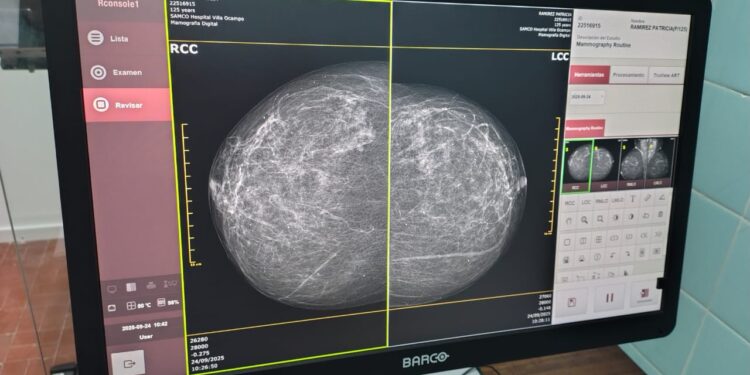

Este moderno equipo ya se encuentra a disposición del Hospital Samco de Villa Ocampo, destinado a reforzar la campaña de prevención y lucha contra el cáncer en toda nuestra región.

Tres mujeres fueron las primeras pacientes en someterse a estudios con el nuevo equipo, gracias a la derivación de LALCEC. Villa Ocampo. Un momento histórico que marca el inicio de una nueva etapa para la salud preventiva en nuestra ciudad.